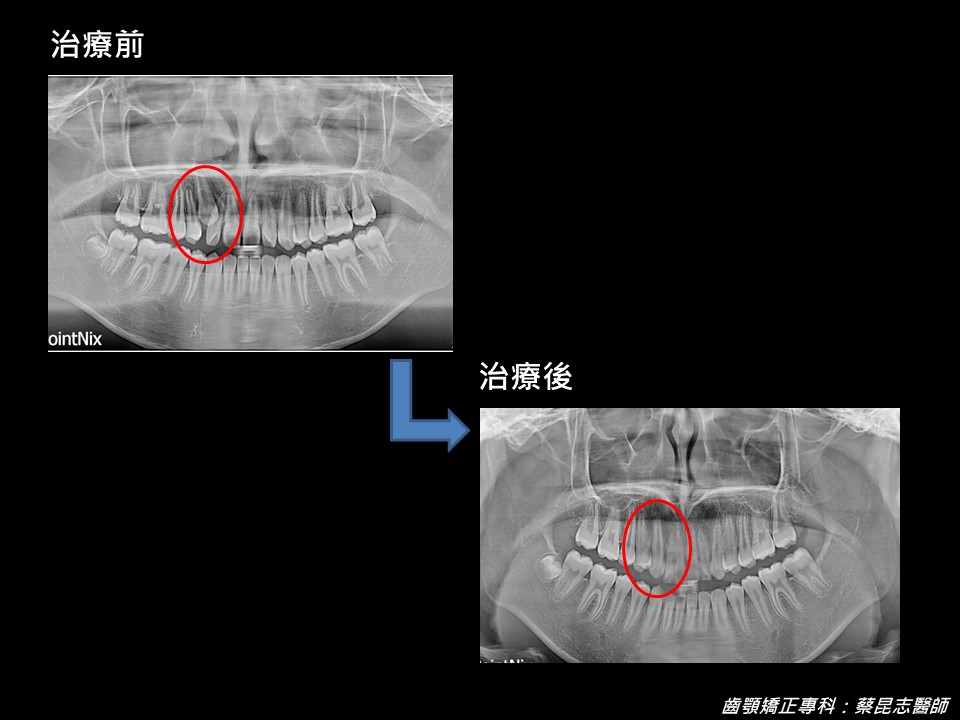

經X光片檢查後,得知是因為右上顎犬齒阻生,所造成的現象。

採用的治療計畫是決定避免拔牙,保留阻生犬齒,矯正撐開適當空間後,再將阻生犬齒拉出排齊。並將上顎偏右的門齒中線,向左移動以對齊下顎中線。